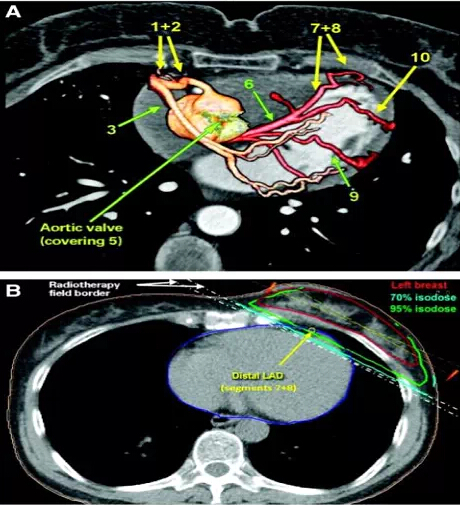

(1)心脏或前降动脉(LAD)剂量更低,降低了心源性死亡风险

质子在乳腺癌治疗中有着明显的优势,能够降低心脏或前降动脉(LAD)剂量及心源性死亡风险,而最新的IMPT技术,让质子治疗更加如虎添翼。